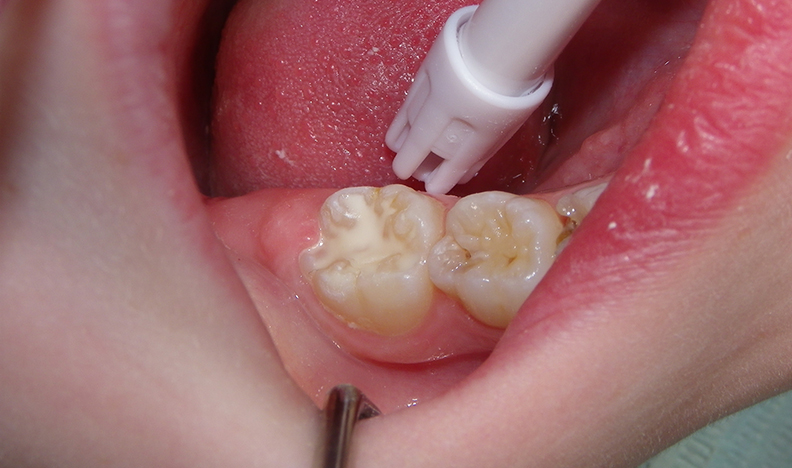

This quick photo series shows the step-by-step process of placing a sealant onto the grooves of an adult molar of a six-year-old. First, air abrasion is used to mechanically remove any loose surface debris or contaminants. Secondly, an acid gel is applied to the surface to be sealed. Finally, a sealant is applied to the surface and allowed to set. For the sharp-eyed, the sealant used was GC Fuji Triage, a glass ionomer sealant that while not as wear-resistant as the more commonly used resin sealants, is more moisture-friendly (ie: contamination resistant) and releases fluoride. The fluoride release allows the underlying enamel to be strengthened over time, making it more decay-resistant for the future.